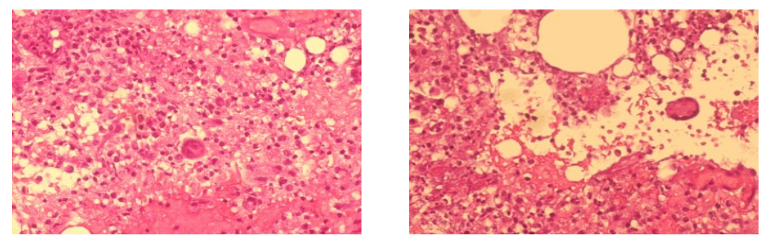

Kết quả giải phẫu bệnh cho thấy tổn thương mô hoại tử dạng bã đậu, tế bào Langhans – đặc trưng của bệnh lao. Xét nghiệm GeneXpert khẳng định sự hiện diện của vi khuẩn lao (Mycobacterium tuberculosis).

Hình ảnh cung cấp là ảnh nhuộm mô học trường hợp viêm lao vú